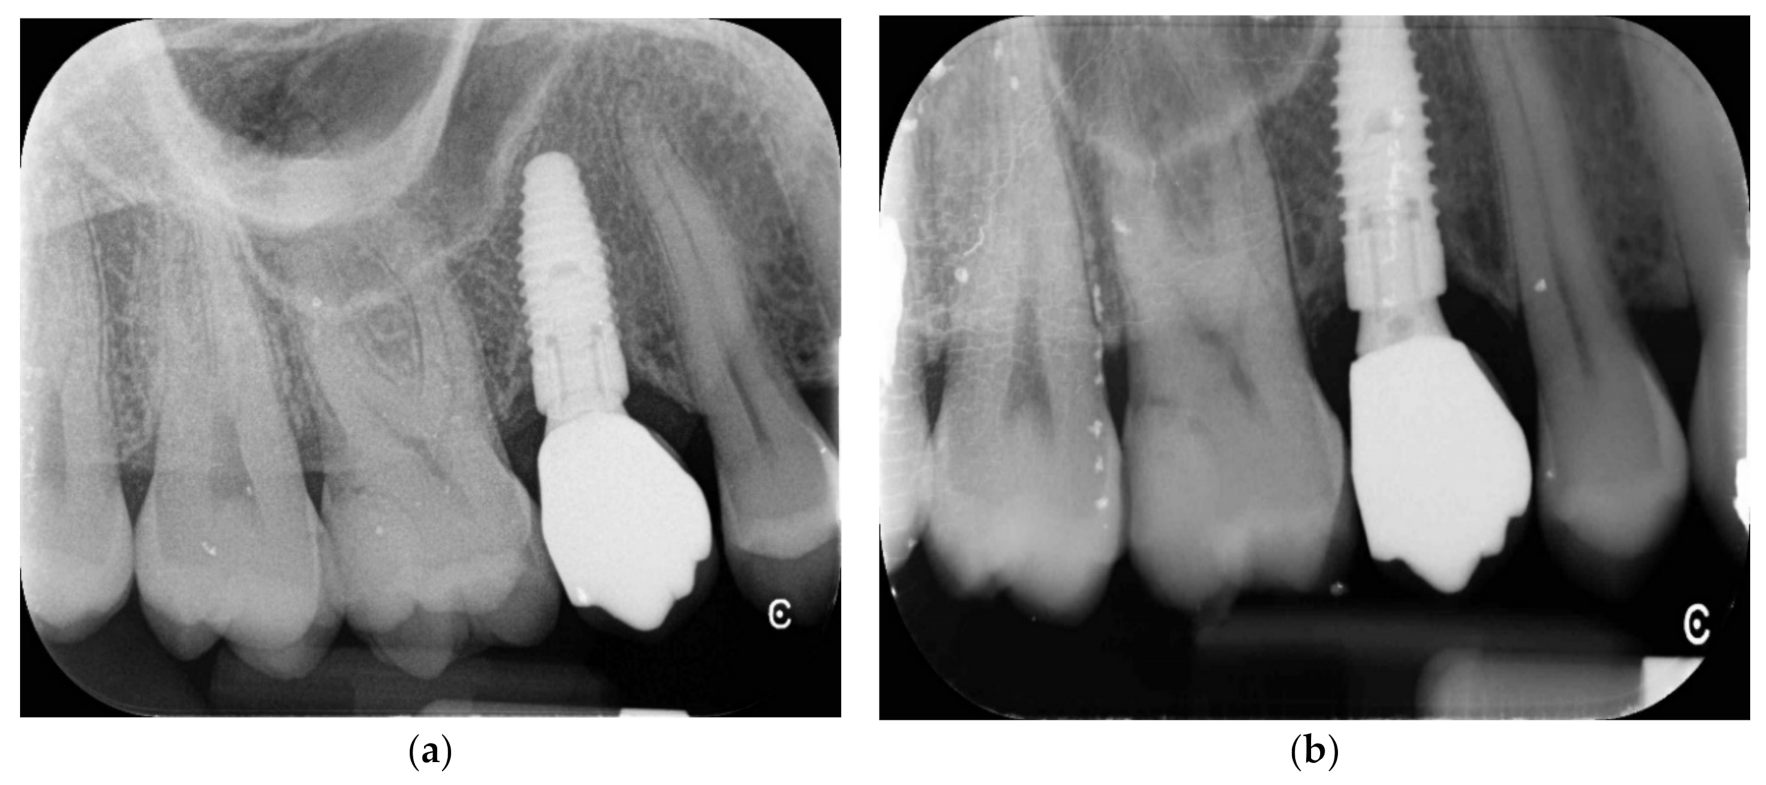

After six months of undisturbed healing, the second stage surgery was performed and an open-tray impression was taken using a polyether material (ImpregumTM, 3M ESPE, Seefeld, Germany). A temporary screw-retained acrylic crown, (Brent Resin top lign) was delivered one month after the second surgery. Three months later, a definitive impression was made using the same polyether material (ImpregumTM, 3M ESPE) with a customized open tray. Finally, a computer-aided designed/computer aided manufactured (CAD/CAM), screw-retained, zirconia-ceramic (Zirconia multilayer Orodent 1200 MPA) prosthesis was delivered and the occlusion was adjusted. Patients were followed once per year, for five years after loading (Figure 5 and Figure 6a,b).

Figure 6.

(a,b) Periapical X-rays at 5 years follow-up.